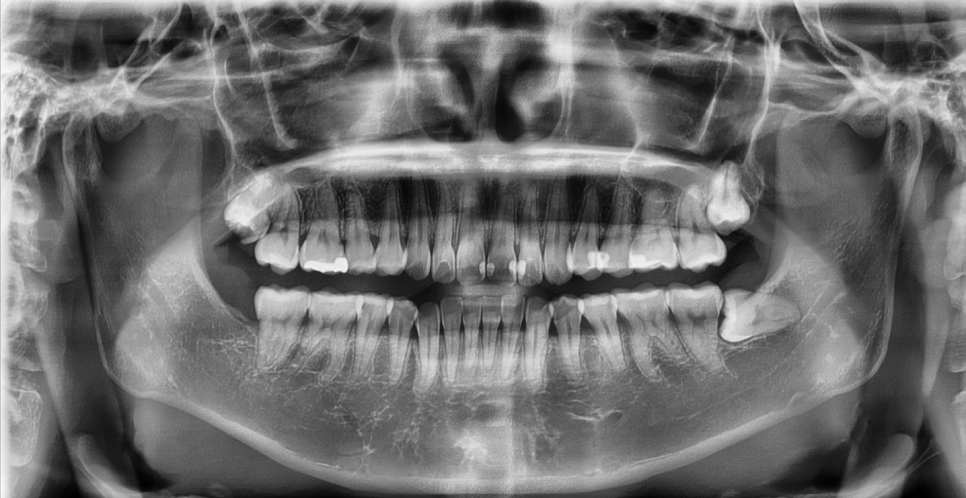

Checking whether tooth reduction could be minimized

Here are the overall findings after examining the panoramic X-ray, intraoral scanner, and bite check.

There was enough tooth structure remaining in the front teeth, and the gum line was also healthy.

In such cases, treatment can be performed with little to no reduction, or even without reduction, while preserving the natural teeth as much as possible.

Most importantly, there was not a single tooth that needed to be heavily shaved for the veneers, so this was the ideal case for possible no-prep laminate veneers.